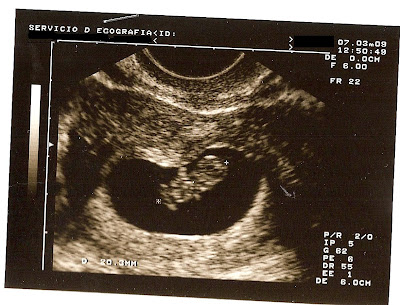

Y efectivamente, estaba embarazada. Esa raya se fue tiñiendo más y más y apenas unas semanas más tarde pudimos ver una gambita latiendo en mi interior.

Esta ecografía nos la hicimos estando de 8+5.

Me encantó cómo le «retrararon» y estuvo mucho tiempo pegada en el frigorífico.

De hecho, ha estado puesta hasta hace bien poco.

Como no sabíamos si era niño o niña, nada más quedarnos embarazados decidimos dirigirnos a él como «embri» y así le estuvimos llamando bastante tiempo, hasta que finalmente elegimos su nombre (incluso tiempo después).

Siempre que pasábamos por el frigorífico le dábamos un besito, a esta ecografía y a otras que fui poniendo.